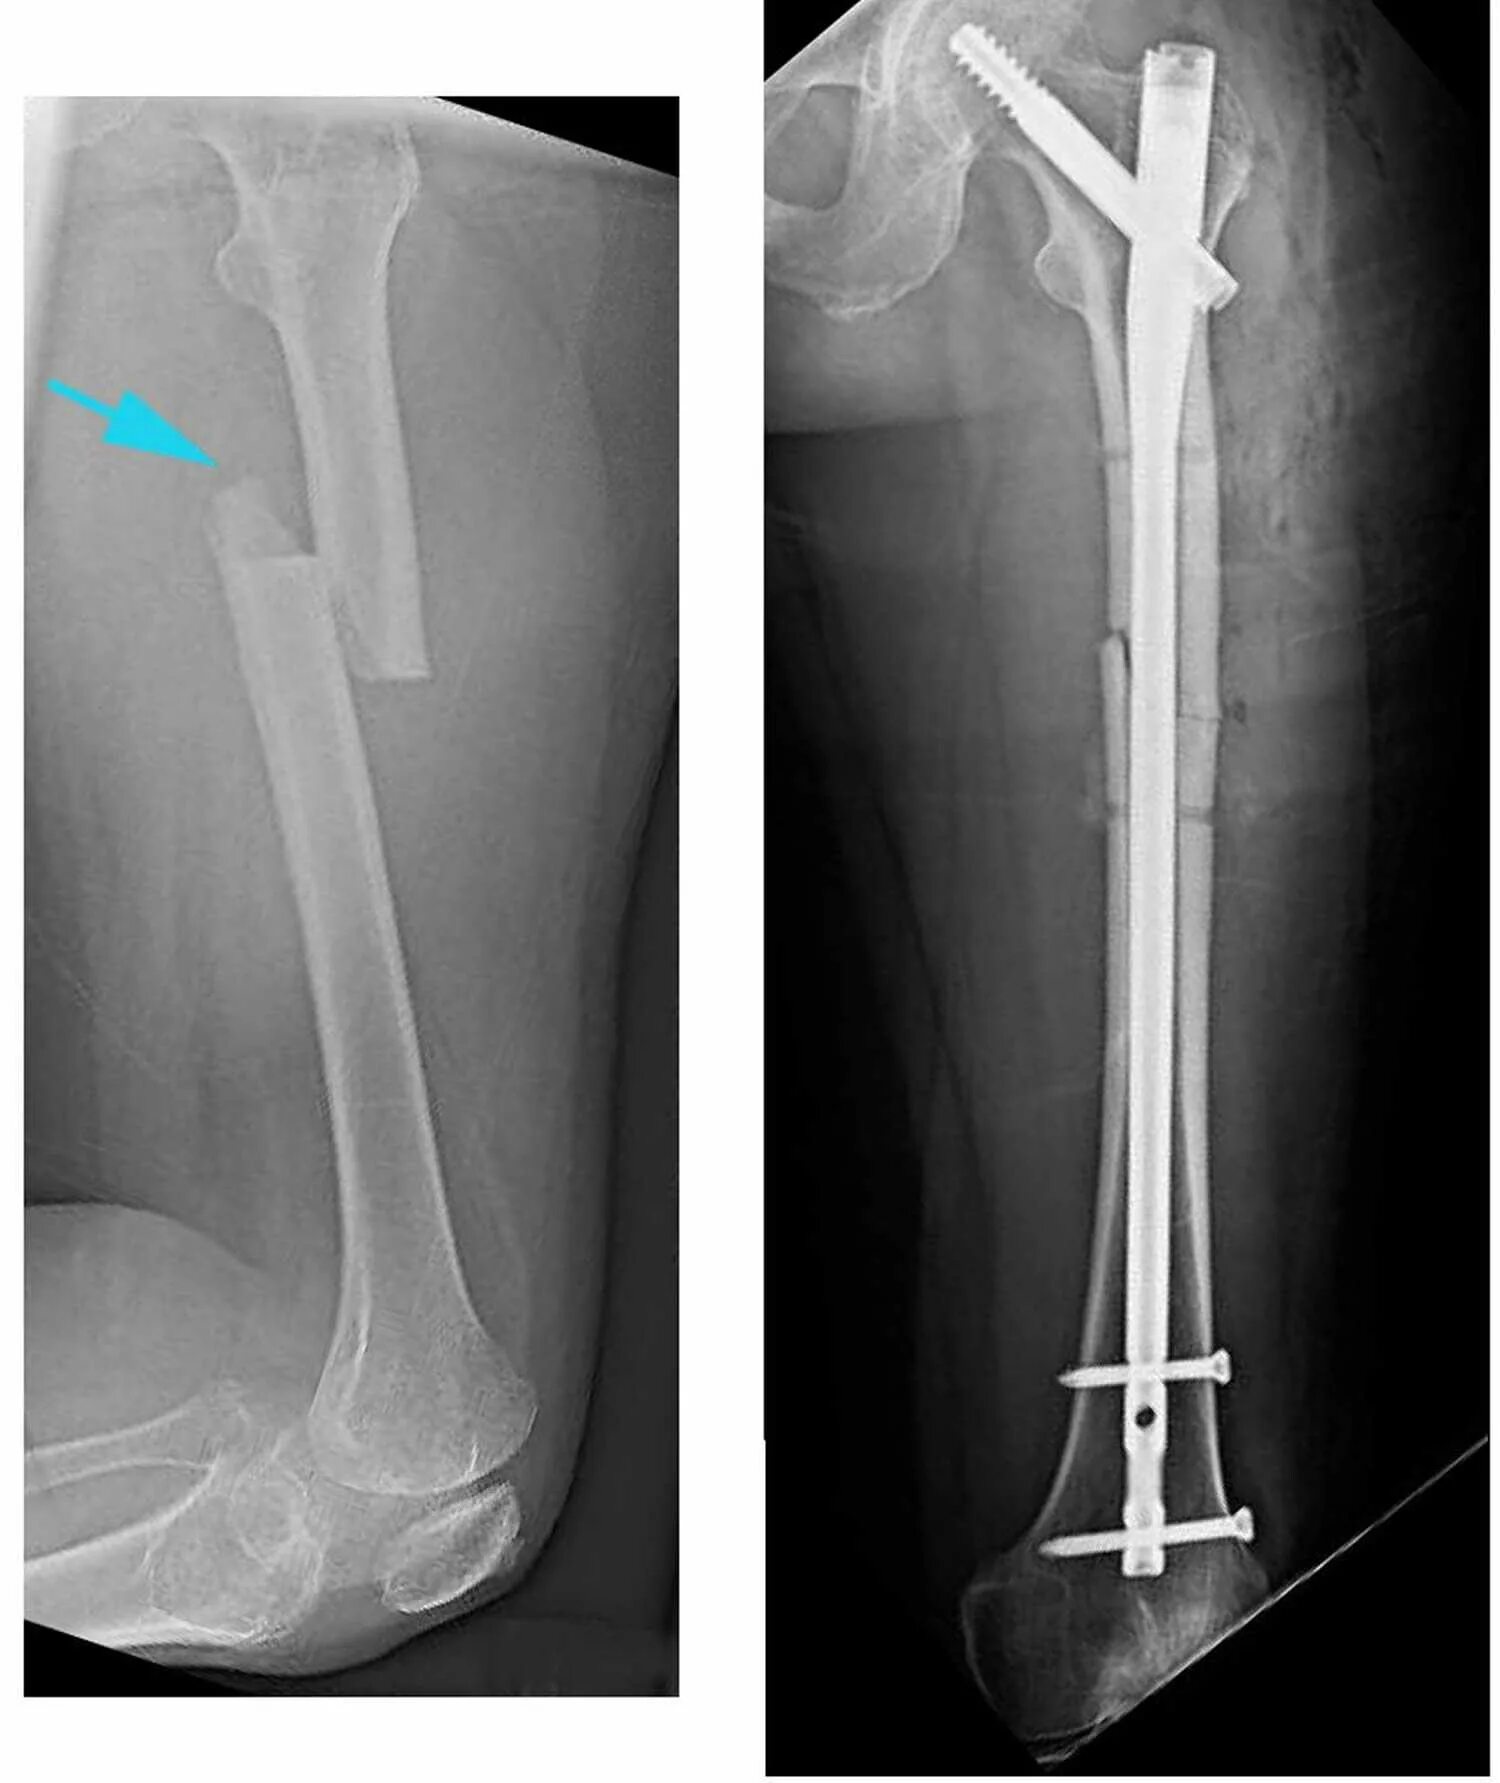

Через перелом бедра